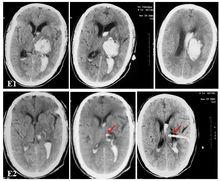

重型腦幹出血是指腦幹出血血腫量>5 ml,伴明顯意識障礙(意識分級≥Ⅲ級或GCS評分≤12分者[1]。由於重型腦幹出血起病兇險,死亡率高,可達70%~80%,而出血量與患者預後密切相關,國內患者可見外科手術治療(開顱血腫清除術,立體定向手術等)成功的報導,但手術難度大,尚不能普及,因此臨床上仍以內科保守治療為主。本文回顧性分析我院近十年來19例經側腦室穿刺持續引流治療重型腦幹出血患者臨床資料,通過積極的搶救和護理,獲得較好效果,現報導如下。 1 臨床資料

男15例,女4例,年齡38歲~68歲,平均年齡52.7歲,患者意識狀況分級Ⅲ級~Ⅴ級,GCS評分≤12分,頭顱CT/MRI證實為腦幹出血,多田氏公式計算血腫量>5 ml。存在高血壓病史11例,嗜煙、酒4例,動脈粥樣硬化2例,病因不詳3例。發病至治療時間為1 h~72 h。

GCS評分:12分~9分10例,8分~4分6例,3分3例,平均7分;嘔吐18例,四肢不同程度無力表現19例,去腦強直發作3例,頭痛15例,眩暈10例,發病初期血壓為(20~30)/(12~18)kPa,中樞性呼吸障礙16例(急促深長呼吸10例,失調式呼吸、潮式呼吸各3例),中樞性高熱6例,雙瞳孔異常17例(不等大6例,針尖樣大小9例,散大2例),雙眼下斜視4例,雙眼分離斜視3例,雙眼固定5例,顱神經麻痹3例,球麻痹表現2例,病理征陽性5例,腦膜征陽性4例。

1.3 治療方法

患者入院後經予脫水降顱壓,降低腦代謝,抗感染,保護胃黏膜等對症治療,治療中行氣管切開術14例,需呼吸機輔助控制呼吸8例。19例內科治療+單側側腦室穿刺持續腦脊液外引流術[1],其中5例經腦室引流管注入東菱精純克栓酶或尿激酶溶解血塊,2例分別進行1次,5次腰穿腦脊液置換術,腦室引流時間4 d~50 d,平均16.6 d。

2.2 結果

見表1。表1 19例重型腦幹出血患者治療結果比較例(略)